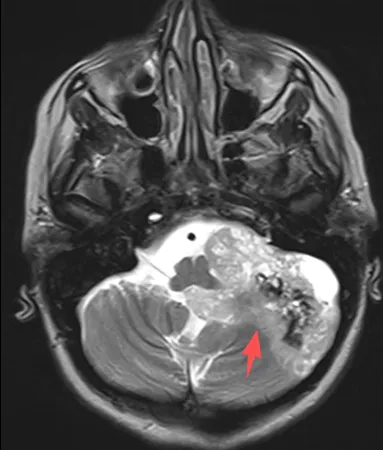

北京天坛医院联合INC巴特朗菲教授展开强强合作。术中发现,肿...